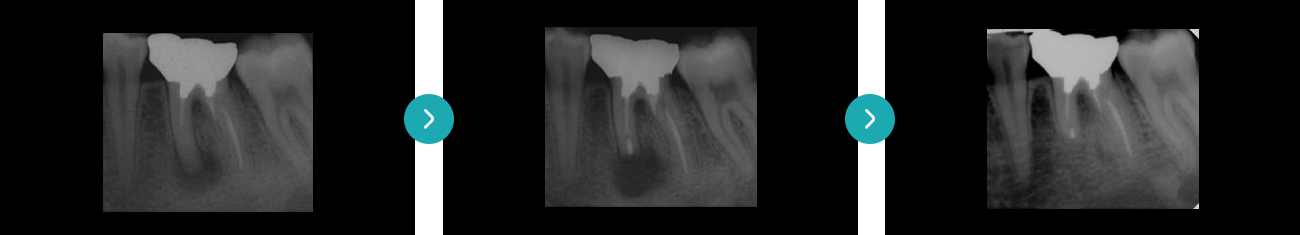

치아재식술의 핵심은 치아를 손상없이 발치하였다가 다시 심는 기술입니다.

더 이상 살릴 수 없는 것 같던 치아도 다시 살려 심으려는 드림플란트치과병원의 노력이 담겨있습니다.

치아재식술은 치아를 감싸고 있는 치근막을 그대로 보존하여

치료해야하는 고난이도 술식입니다.

드림플란트치과병원의 의료진은 수많은 치아재식술 경험을 통해

다양한 노하우를 지니고 있습니다.